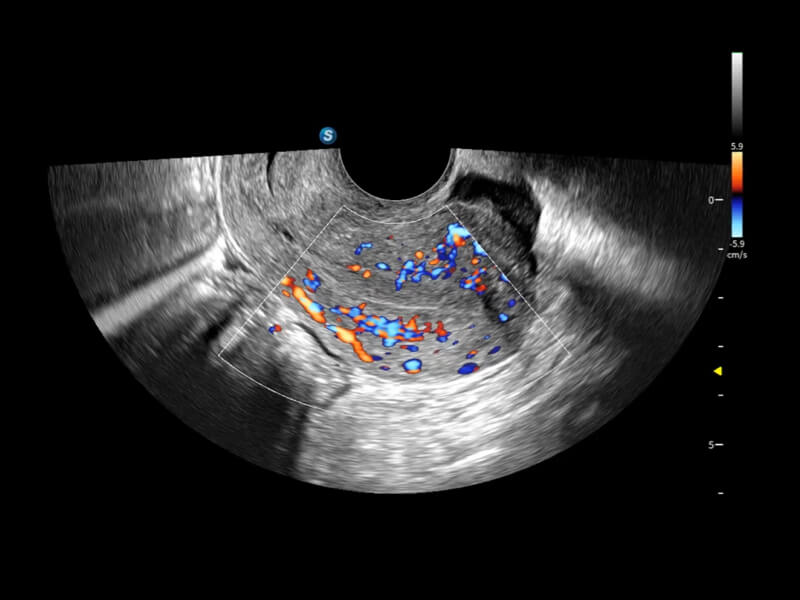

Exquisite Bildklarheit & Hämodynamik

Bildqualität steht stets im Zentrum verlässlicher klinischer Ergebnisse. Das S70i Fenix führt weiterentwickelte Schallköpfe mit herausragender 2D-Bildklarheit und hoher Farbsensitivität ein – für eine sicherere Beurteilung anatomischer Strukturen und pathologischer Veränderungen.

Fein abgestimmte hämodynamische Lösung

Eine Vielzahl hämodynamischer Diagnosetechniken ermöglicht eine effektive Blutflusssignaldetektion in verschiedenen Szenarien.

• Bright Flow

Bright Flow bietet eine 3D-ähnliche Farb-Doppler-Flow-Visualisierung ohne den Einsatz eines Volumenwandlers, wodurch die Grenzdefinition der Gefäßwände verstärkt wird.

• Micro F

Micro F unterscheidet subtile Blutflusssignale effizient von überlagerter Gewebebewegung und ermöglicht eine erhöhte Empfindlichkeit sowie räumliche Auflösung in der hämodynamischen Darstellung.